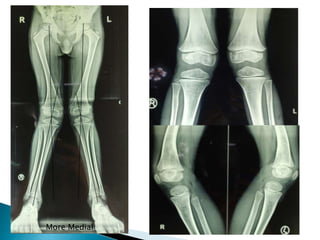

 6 y old boy of Vitamin D Deficiency B/L Genu

Valgum having Tibiofemoral angle 16 degree

Intermalleolar distance of 11cm, Q angle of

15 degree with 0-140 ROM of knee joint

 Imaging – Full length Xray of bilateral Lower

limbs, xray of wrist, knee

 Mechanical Axis deviation ???? Stevans Zones